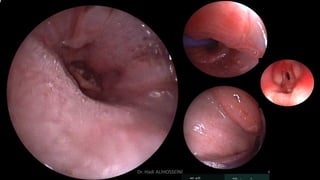

Elongated Soft Palate

 9 aylık kısırlaştırılmış Dişi İran kedisi

 Şikayeti: Sürekli Nüks eden Pulmoner Ödem

 Endoscopic evaluation of the pharynx and larynx:

 Overlong Elongated Soft Palate

 It was overlying the epiglottis.

 Cerrahi Partial resection

 Tüm Solunum problemleri giderildi.